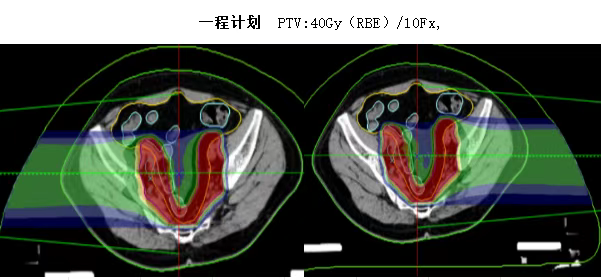

以下为碳离子治疗计划

碳离子治疗的三大核心优势

✅ 精准杀伤肿瘤,保护正常组织

●利用Bragg峰特性,高剂量精准覆盖肿瘤,同时尽量避开肠道。